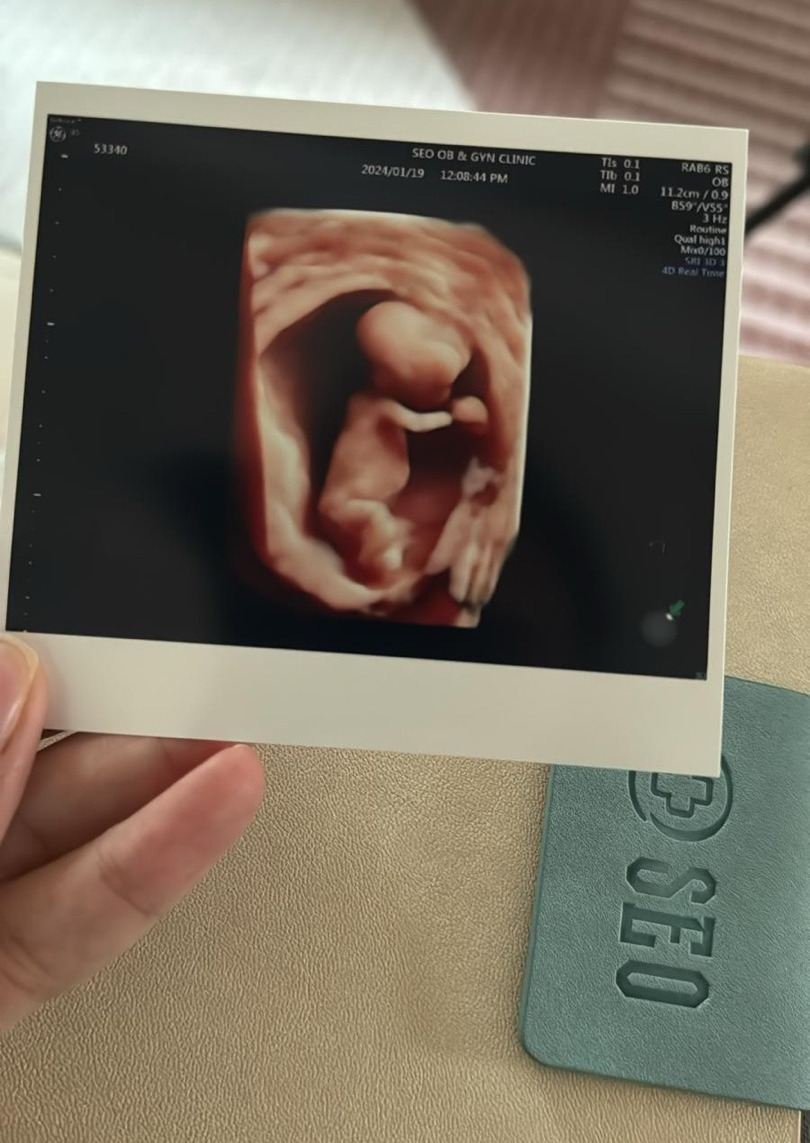

와이프 뱃속에 10cm가량 되는 생명이 숨 쉬고 있다. 한 생명이 새 생명을 잉태하고 있다니, 이 얼마나 신비로운 일인가? 이 삶은 도대체 무엇이란 말인가? 나 또한 엄마의 뱃속에서 이렇게나 작디작은 존재로 시작했을 터인데, 서른 다섯 해 동안 무럭무럭 자라 이제는 누군가의 아빠가 될 준비를 하고 있다니...